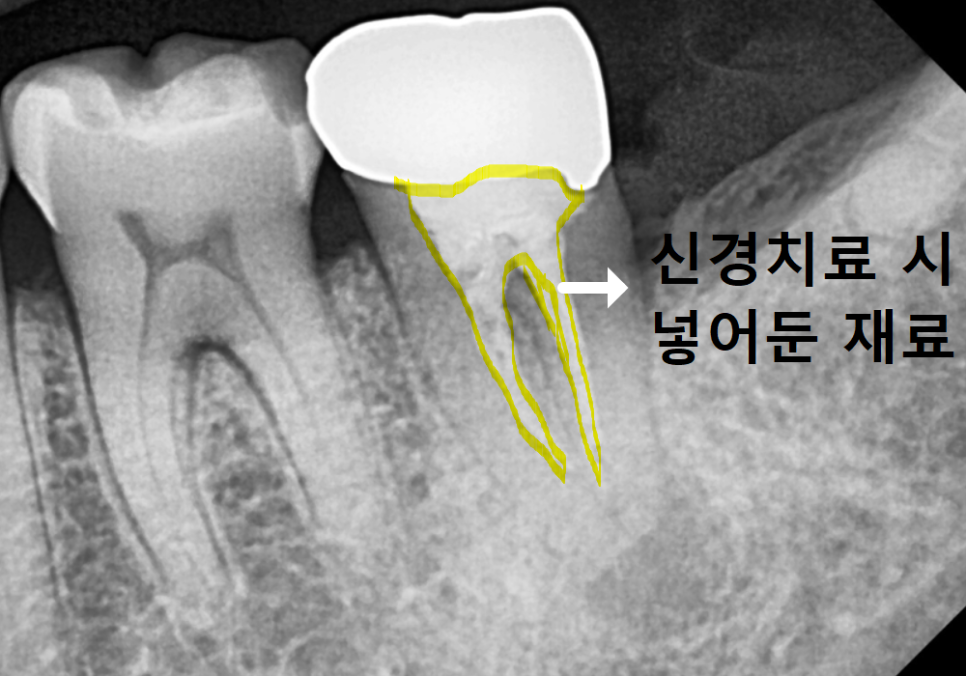

250508

재신경치료는 이미 한 번 손을 댄 곳을

다시 청소하는 작업인데요.

기존에 채워 넣었던 단단한 재료들을

일일이 걷어내야 할 뿐더러,,,

이미 그 안에서 세균이 더 깊숙이 자리를 잡았다면

치료의 성공 가능성이 뚝 떨어지게 됩니다.

재신경치료 시, 기존 재료를 걷어내고 소독과정을 여러번 거침